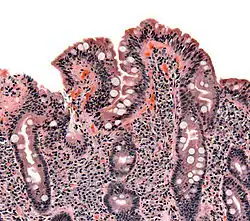

Histologie

Wird der Verdacht auf das Vorliegen einer Zöliakie durch positive Antikörperbefunde erhärtet, kann die Diagnose entsprechend den Empfehlungen der Europäischen Gesellschaft für pädiatrische Gastroenterologie, Hepatologie und Ernährung (ESPGHAN) durch eine Dünndarmbiopsie gesichert werden. Dabei werden – heutzutage zumeist mittels einer Magen- und teilweisen Dünndarmspiegelung (Gastroduodenoskopie) – kleine Schleimhautproben aus dem absteigenden Duodenum entnommen. Es gelingt nicht immer, die geeignete Lokalisation zur Biopsie zu finden. Die entnommenen Gewebestücke werden von einem Pathologen feingeweblich am Mikroskop untersucht, wobei zunächst bei geringer Vergrößerung (50fach) der Aufbau der Dünndarmschleimhaut beurteilt wird. Bei stärkerer Vergrößerung wird anschließend untersucht, ob die Schleimhaut eine Vermehrung von Entzündungszellen aufweist. Für die Diagnose einer Zöliakie sind hierbei die innerhalb der Deckschicht (Epithel) gelegenen Lymphozyten entscheidend. Bei grenzwertigen Befunden kann die histologische Standardfärbung noch um eine Immunhistologie erweitert werden, mit der sich die intraepithelialen Lymphozyten besser quantifizieren lassen. Goldstandard für die Beurteilung der Dünndarmbiopsie sind die sogenannten Marsh-Kriterien: Zahl der in die Schleimhaut eingewanderten Lymphozyten, Zottenlänge im Verhältnis zu den Krypten, Zellteilungsrate, Anzahl der Entzündungszellen in der Lamina propria (Darmwandschicht direkt unterhalb des Epithels) und Beurteilung des Bürstensaums in einer speziellen Färbung (PAS-Färbung). Für die Diagnose Zöliakie sind die Marsh 2- oder Marsh 3-Kriterien erforderlich:

- Marsh 2: ≥ 25 intraepitheliale Lymphozyten / 100 Enterozyten + Hyperplasie der Lieberkühn-Krypten

- Marsh 3: ≥ 25[33][34] intraepitheliale Lymphozyten / 100 Enterozyten + Kryptenhyperplasie + Zottenatrophie.

Eine andere, beispielsweise infektiöse Ursache der Entzündung sollte durch eine Suche nach Mikroorganismen wie Tropheryma whipplei, Giardien und Kryptosporidien ausgeschlossen werden. Die 1990 revidierten diagnostischen Kriterien der ESPGHAN fordern zudem eine klare klinische Besserung nach Einleitung der Therapie. Kontrollbiopsien, die früher noch üblich waren, sind demnach nur bei spezieller Indikation angezeigt wie zweifelhaftem klinischem Erfolg unter glutenfreier Diät, Zweifel an der Initialdiagnose oder zur Abgrenzung gegen eine vorübergehende Glutenintoleranz.[14]